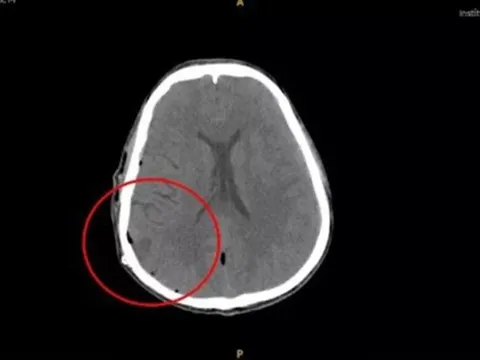

Đau nhức đầu khi đi bơi, nam thanh niên rơi vào hôn mê do xuất huyết não

VTV.vn - Bệnh viện Đa khoa Xuyên Á Tây Ninh vừa cấp cứu và điều trị cho nam bệnh nhân nguy kịch do xuất huyết não.

Nam thanh niên bị xuất huyết não nguy kịch sau khi đi bơi

Nạn nhân bị nhức đầu sau khi đi bơi sau đó hôn mê sâu, xuất huyết não. Trước đó anh nhảy xuống hồ bơi mà không biết nước cạn, đầu va đập với nước gần đáy hồ.